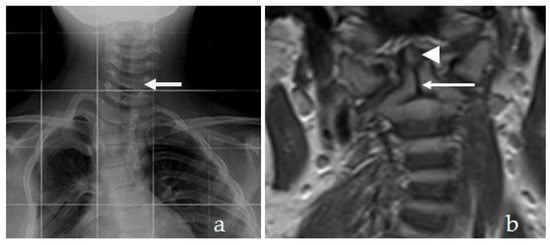

Reformatted CT scan of the craniocervcial and the cervical vertebrae of the proband showed odontoid hypoplasia secondary to neurocentral synchodrosis and defective formation of the cervical vertebrae in connection with synchondrosis. The latter is the development of union between two bones by the formation of either hyaline cartilage of fibrocartilage. A synchondrosis is usually temporary and exists during the growing phase until the intervening cartilage becomes progressively thinner during skeletal maturation and is ultimately obliterated and converted into bone before adult life. In other words, a synchondrosis is a cartilaginous joint. It allows only slight movement between bones compared to the synovial joint, which has a much greater range of movement. The process of ossification within the centrum of the vertebral body is similar to that of tertiary ossification. Longitudinal growth mostly occurs at the chondro-epiphyseal portions of the end-plates. In this patient, it was obvious that synchondrosis was a permanent rather than a temporary process. Reformatted Coronal CT scan of the cervical spine showed butterfly vertebrae (defective formation), note the detached cephalic part of the odontoid process (arrowhead) in connection with extensive cervical spine synchondrosis causing the mal-development of butterfly vertebrae (Figure 1a). Reconstruction CT scan of the cervical spine showed atlanto-axial dislocation (arrows). Both parents experienced low backpain since their late adolescence (spondylolisthesis was the diagnosis). AP radiograph of the lumbar vertebrae at the age of 32-year-old mother showed osteoarthritis of the facet joints of L5 (arrow) associated with diminution of the heights of L4/5. Note the increased level of calcification that signifies facet arthritis. Surprisingly, the AP pelvis radiograph of the mother at age of 32 years showed incidental diagnosis of ossification of the abdominal aorta. The mother is asymptomatic, but such finding is of utmost importance. Ossification of the abdominal aorta signifies a state of subclinical atherosclerosis with subsequent vascular hazards-red arrowhead (Figure 2a). Sagittal spine MRI of the 38-year-old father showed dysplastic spondylolisthesis of L4/5 (arrow) that might leads to spinal stenosis (Figure 2b). Phenotype/genotype of the family with spondylo-meg-epiphyseal-dysplasia appears in Table 1.

Figure 1. (a). Reformatted Coronal CT scan of the cervical spine showed butterfly vertebrae (defective formation), note the detached cephalic part of the odontoid process (arrowhead) in connection with extensive cervical spine synchondrosis causing the mal-development of butterfly vertebrae. (b) Reconstruction CT scan of the cervical spine showed atlanto-axial dislocation (arrows).